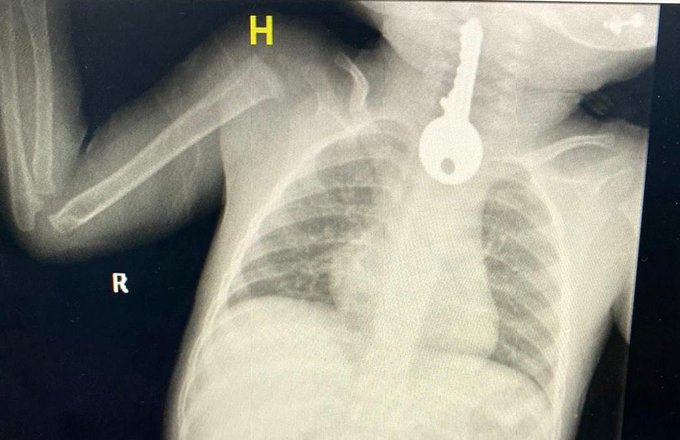

نجح فريق طبي بمحافظة الطائف في إنقاذ طفل كاد أن يفارق الحياة بعد أن أحضر إلى قسم الطوارئ في حالة حرجة.

وأجرى الفريق الطبي عملية للصغير بالمنظار تكللت بالنجاح، إلا أن المفاجأة كانت بما أخرجوه من صدره.

وأوضح مجمع الملك فيصل الطبي عبر حسابه في تويتر، أنه استقبل حالة طفل في وضع صحي حرج يعاني من ضيق في التنفس، مما استدعى تقديم الإسعافات الأولية وإجراء الفحوصات السريرية والإشعاعية.

وكشفت الفحوصات وجود جسم غريب على شكل مفتاح في المريء، وعلى الفور اتخذت الإجراءات اللازمة.

كما أوضح الفريق المعالج للحالة أنه تم على الفور عمل منظار عاجل واستخراج مفتاح حديدي من المريء كاد أن يودي بحياته.

يشار إلى أن الفريق الطبي يعمل اليوم على متابعة الصغير في قسم التنويم تحت رعاية الفرق التمريضية.

وأكد أن الحالة استقرت وخرج الطفل بصحة جيدة.